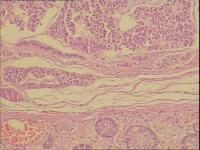

直肠类癌

性别年龄53岁临床诊断

一般病史距肛门5厘米,腺瘤样隆起。

标本名称肠镜

大体所见肉红色组织一块直径0.9CM

神经内分泌肿瘤   行免疫组化标记

神经内分泌肿瘤,G1。

考虑:恶性肿瘤,建议:CgA;NSE等,排除直肠类癌

神经内分泌肿瘤,需做免疫组化协助鉴别并分级。